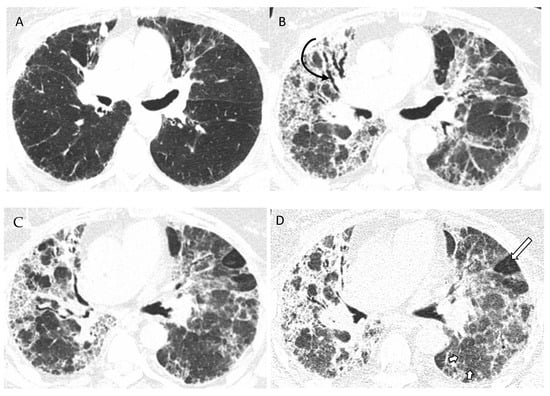

- Chung, M.H.; Edinburg, K.J.; Webb, E.M.; McCowin, M.; Webb, W.R. Mixed infiltrative and obstructive disease on high-resolution CT: Differential diagnosis and functional correlates in a consecutive series. J. Thorac. Imaging 2001, 16, 69–75. [Google Scholar] [CrossRef]

- Barnett, J.; Molyneaux, P.L.; Rawal, B.; Abdullah, R.; Hare, S.S.; Vancheeswaran, R.; Desai, S.R.; Maher, T.M.; Wells, A.U.; Devaraj, A. Variable utility of mosaic attenuation to distinguish fibrotic hypersensitivity pneumonitis from idiopathic pulmonary fibrosis. Eur. Respir. J. 2019, 54, 1900531. [Google Scholar] [CrossRef]

| Mosaic attenuation | Diffuse and subtle GGO | |

| Lung cysts | ||